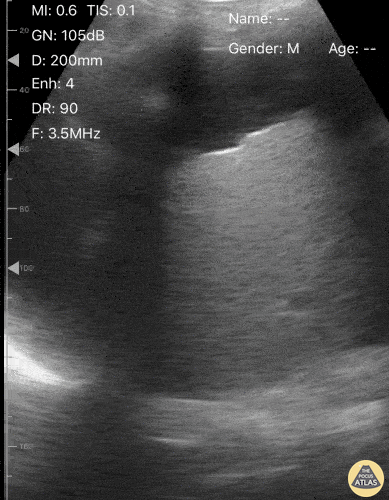

Bowel-GI - Floating Liver

A 59 year old male with known history of alcoholic cirrhosis presented with dyspnea. Physical exam was notable for a distended, non-tender abdomen. POCUS performed on the RUQ using the curvilinear probe revealed the liver “floating” within ascites. This highlights the importance of performing POCUS to guide procedures, as the patient subsequently warranted therapeutic paracentesis. Victor Bang, Emergency Clinician at Hospital das Clínicas de Marília. Co-Founder of Pocus Jedi @vmjbang